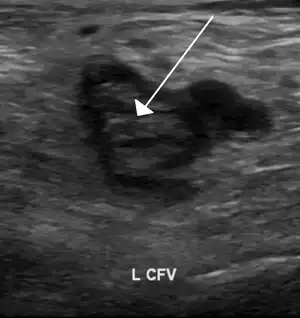

| An ultrasound image demonstrating a blood clot in the left common femoral vein. | |

Thrombophilia (sometimes called hypercoagulability or a prothrombotic state) is an abnormality of blood coagulation that increases the risk of thrombosis (blood clots in blood vessels).[1][2] Such abnormalities can be identified in 50% of people who have an episode of thrombosis (such as deep vein thrombosis in the leg) that was not provoked by other causes.[3] A significant proportion of the population has a detectable thrombophilic abnormality, but most of these develop thrombosis only in the presence of an additional risk factor.[2]